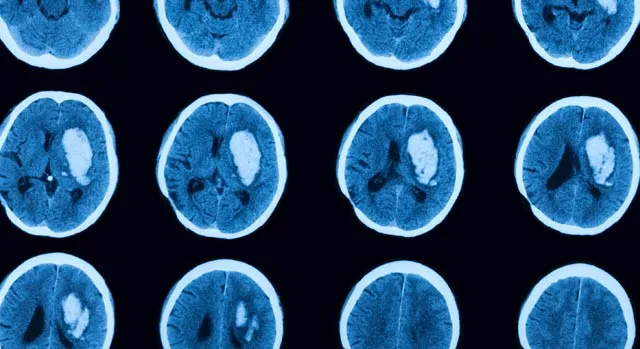

Реабилитация при инсульте начинается после оказания первой экстренной помощи. Задача врачей – правильно диагностировать состояние, чтобы определить тип и масштабы кровоизлияния. Далее назначается комплексная медикаментозная, инвазивная терапия, цель которой – локализовать прорыв и сохранить жизнь пациенту. Что же такое инсульт? Это внезапно возникшая патология мозгового кровообращения, которая продолжается более суток. Именно продолжительность отличает инсульт от классической транзиторной ишемии, симптоматика которой исчезает в течение нескольких часов. В группе риска – люди, страдающие артериальной гипертонией, патологиями сердечного ритма, а также те, кто перешагнул возрастной рубеж в 50 лет. Определить инсульт можно мгновенно по нарушению речевых, двигательных, когнитивных и других функций. Чтобы не запустить процесс деградации тканей, врачи рекомендуют начинать восстановление при инсульте сразу же после минования криза. Почему? В результате пагубного механизма (блокировки кровотока или кровоизлияния) умирает часть мозговых клеток, в частности, отвечающих за вербальную, познавательную активность. Ценна каждая минута! По принципу возникновения, различают следующие виды инсульта: